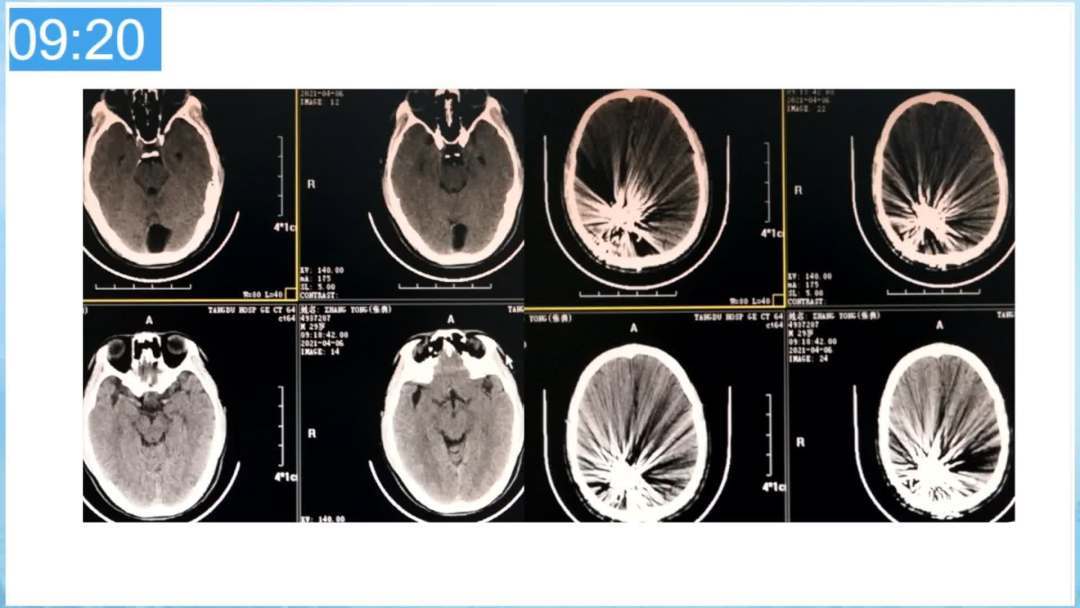

本期为大家特别分享:空军军医大学唐都医院邓剑平教授的精彩会议内容《颅内动静脉畸形的复合手术治疗》,欢迎大家阅读和分享!

合理的复合平台下的综合治疗,针对每一个病变对应不同方法安全性分析,不预设、不排斥,每种技术发挥到最佳,互相保障。